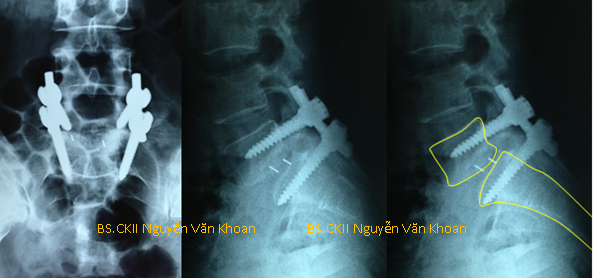

Hình X quang cho thấy bệnh nhân bị trượt đốt sống thắt lưng L5/S1 đã được mổ nắn chỉnh, đặt dụng cụ ốc chân cung với 2 thanh nối dọc, hàn liên thân đốt bằng nêm PEEK.

Có 2 loại nêm PEEK, đó là PEEK cong hình trái chuối và PEEK thẳng hình đầu đạn. Thông thường, một PEEK cong có giá bằng 2 PEEK thẳng. Nêm PEEK là vật liệu tổng hợp bằng chất sừng, không cản quang. Do đó, các nhà khoa học đã dùng một sợi kim loại cản quang luồn vào 2 đầu của nêm PEEK. Mục đích để có thể chụp X quang sau mổ, thấy được vị trí của nêm PEEK trong cột sống có đúng vị trí cần đặt hay không.

PEEK thẳng thường phải dùng 2 con để tạo thế cân bằng giữa 2 thân đốt sống, rất vững. Tuy nhiên, nhiều bác sĩ phẫu thuật viên chỉ sử dụng 1 nêm PEEK thẳng, đặt chéo. Kiểu đặt này sẽ tiết kiệm cho bác sĩ 1 nêm PEEK, nhưng lại không vững bằng và đương nhiên nguy cơ không hàn xương cũng cao hơn. Nêm PEEK cong hình trái chuối (Banana Cage) được thiết kế để đặt ngang theo chiều cong thân đốt sống, sử dụng 1 con, cũng rất vững và cho tỉ lệ hàn xương cao.